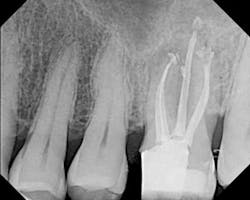

Fig. 1 — Clinical case instrumented with Twisted Files* and obturated with RealSeal One Bonded Obturators.*